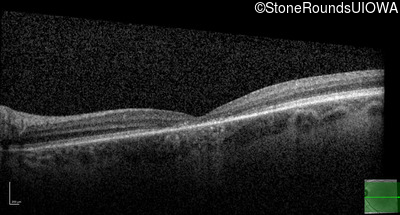

Age at visit: 17 years

OD OS

Age at visit: 17 years (Visit 2)

Age at visit: 21 years

Age at visit: 23 years

Age at visit: 25 years